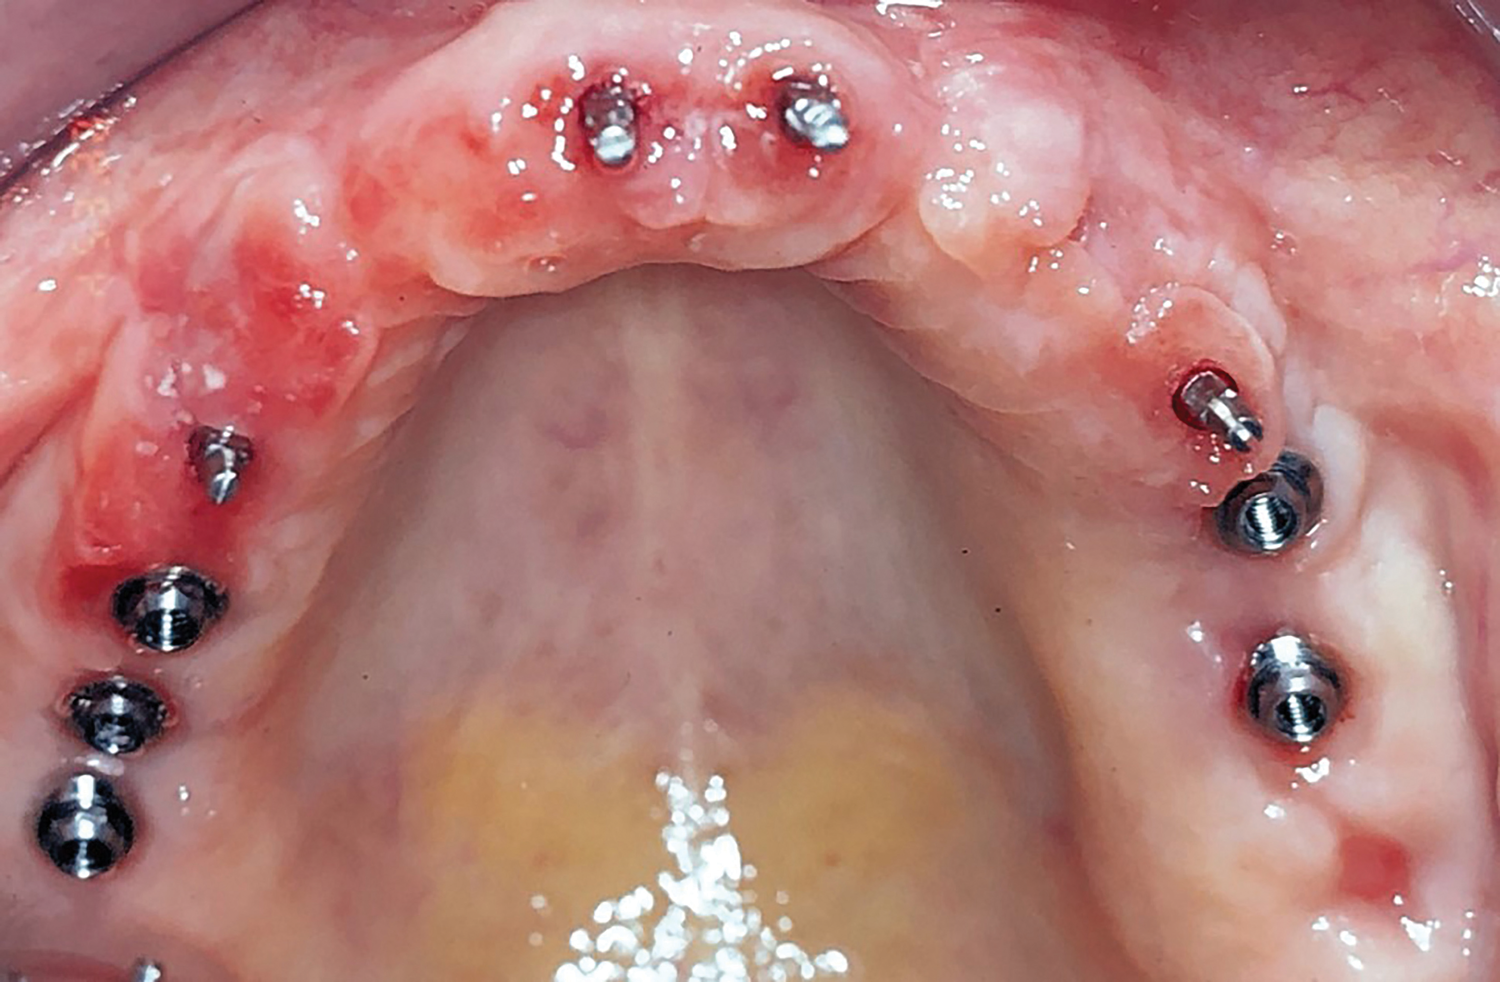

Fig 1. Initial occlusal view of maxillary arch.

Figure 1

Clinical and radiographic examinations were carried out and revealed multiple missing teeth, nonrestorable teeth, periodontal disease, and bone loss (Figure 1 and Figure 2). The final treatment plan that was then proposed to and accepted and signed by the patient included extraction of all remaining teeth in the maxilla, delivery of a provisional fixed restoration supported by six transitional implants, bilateral sinus augmentation, placement of eight to 10 conventional implants, and an implant-supported porcelain-fused-to-metal or hybrid (screw-retained) restoration. For the mandible, the plan included extraction of teeth Nos. 29 and 32 and placement of implants in sites Nos. 18, 19, 20, 29, 30, and 31, with three splinted implant-supported fixed crowns on each side. The patient, however, decided to proceed only with the maxillary restoration and have the mandibular implants and restorations done in private practice.